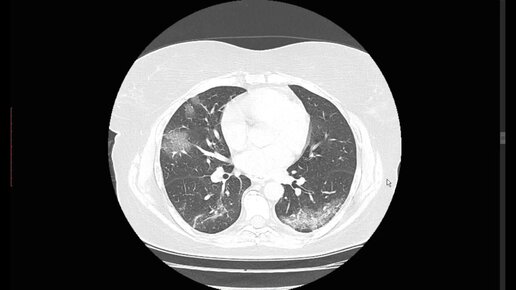

Признаки коронавируса на КТ легких и рентгене